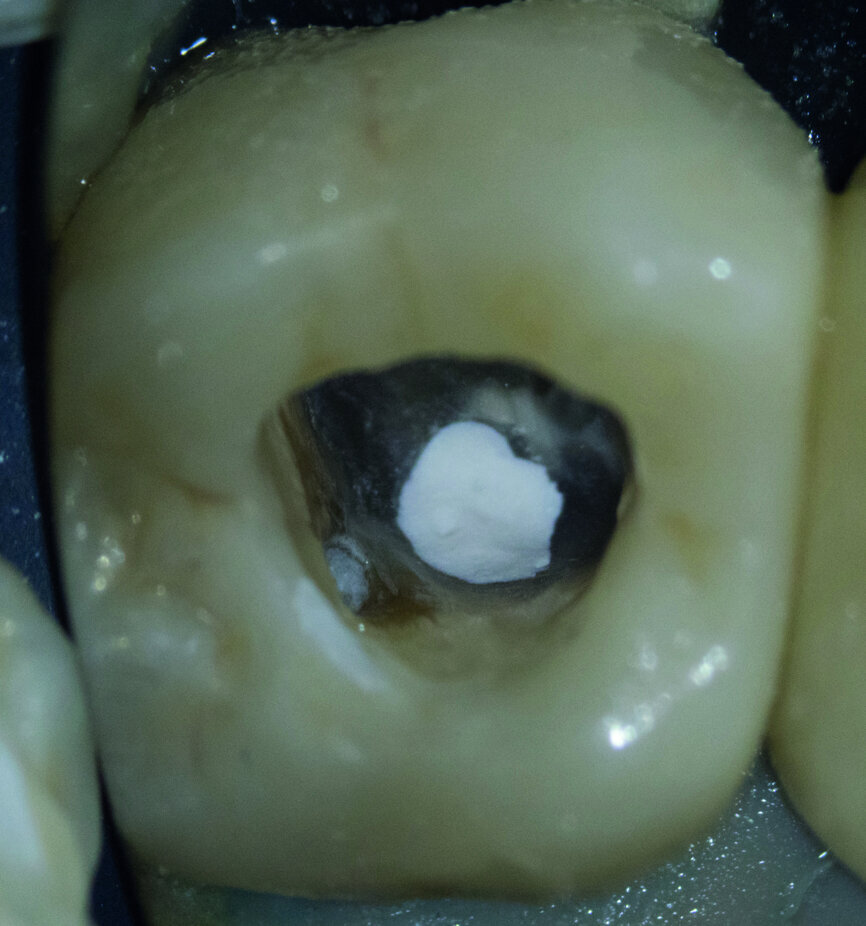

Fig. 4 : L’orifice a été provisoirement fermé avec un matériau d’obturation hygroscopique provisoire et recouvert d’un composite fluide de couleur bleue.

Fig. 9 : Maîtres cônes mis en place dans le canal.

Le matériau d’obturation du canal radiculaire (Figs. 9 et 10) a été enfoui aussi profondément que possible afin de parvenir à une surface de rétention adhésive maximale pour la fermeture post-endodontique, puis un sablage par Al2O3 a été réalisé (Fig. 11). Ensuite, everX Flow de teinte translucide (Bulk) a été utilisé et a comblé un hiatus dans mon protocole de traitement. Le produit s’écoule très bien, sans formation de bulles, dans la profondeur des canaux et il permet donc l’obturation des petits canaux radiculaires avec un matériau composite renforcé en fibres de verre (glass fibre reinforced material, FRC). Dans ce cas, j’ai utilisé everX Posterior, de viscosite plus élevée, selon la technique dite de chasse-neige.